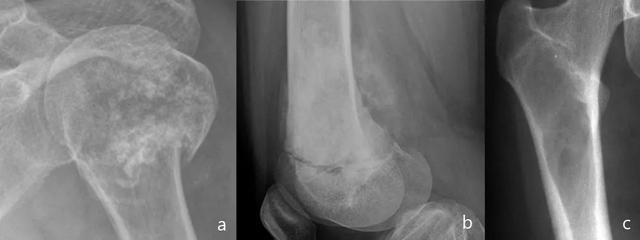

图9:患有淋巴瘤的患者的继发性骨受累。左肱骨颈和头部的溶解性病变呈现渗透模式(a)。股骨干的局部病变,边缘不明确,产生骨内膜扇形切迹(b和c)。